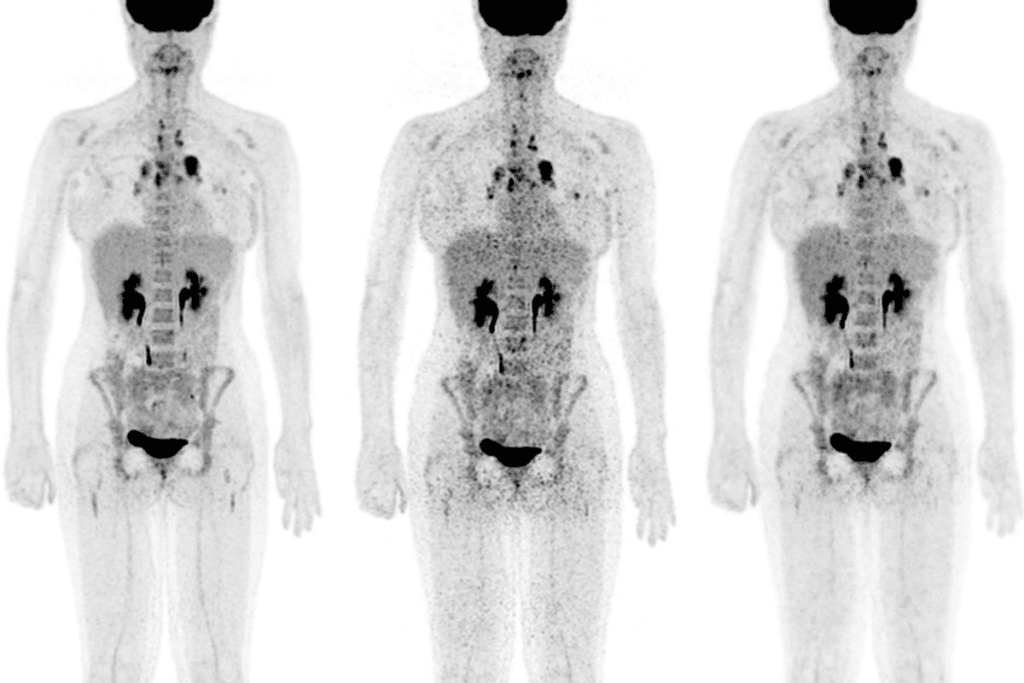

Treatment Monitoring with PET/CT Imaging

Monitoring how well cancer treatment is working is key. PET/CT scans play a big role in this. They help us see if a patient is responding well to treatment, so we can adjust their care plan as needed.

Tracking Cancer Treatment Effectiveness

PET/CT imaging lets us check if cancer treatment is working. It looks at how active tumors are. This is important to know if the treatment is effective.

Early assessment of treatment response is a big plus of PET/CT imaging. It shows how a tumor reacts to treatment early on. This helps us decide if we should keep or change the treatment plan.

Identifying Early Response to Therapy

Being able to see how therapy works early is very important. PET/CT scans can spot changes in tumor activity soon after treatment starts. This gives us important clues about how well the treatment is working.

With PET/CT imaging, we can tell apart living tumor cells and dead or scar tissue. This is really helpful after surgery or radiation. It helps us accurately see how well the treatment is working.

Detecting Recurrence Before Symptoms Appear

PET/CT imaging is also great at finding cancer that comes back early. Regular scans can spot tumors coming back when they are easier to treat.

Guiding Treatment Plan Adjustments

The info from PET/CT scans helps us change treatment plans. By knowing how a patient’s cancer is reacting to treatment, we can make better choices for their care.

Whether it’s changing chemotherapy, planning more surgeries, or looking at other treatments, PET/CT imaging gives us the insights we need. It helps us tailor treatment to each patient’s unique needs.